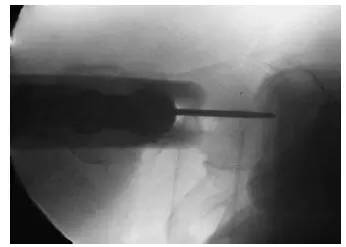

图 5. 股骨近端实时透视影像下,可见髓内针位于股骨中央,导针也位于股骨干和股骨头中心。